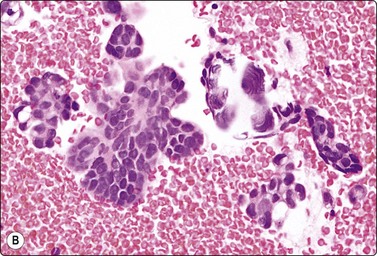

Embryonal carcinoma (Figs 13.33 and 13.34)14,58-61,63,65,66

image image

Fig. 13.33 Embryonal carcinoma

(A) Adenocarcinoma-like tissue fragment of large malignant cells with large vesicular nuclei, coarse chromatin, prominent nucleoli; prominent cytoplasmic vacuolation (MGG, HP); (B) Fragment of undifferentiated mesenchymal tissue right; cluster of malignant epithelial cells with large vesicular nuclei and prominent large nucleoli (H&E, HP) left.

image

Fig.13.34 Embryonal carcinoma

Tissue section corresponding to Fig. 13.33B (H&E, IP).

Criteria for diagnosis

Cell-rich smears,

Frequent three-dimensional clusters,

Occasional tendency to acinar and microglandular grouping,

Large vesicular, obviously malignant nuclei, large nucleoli,

Indistinct cell borders,

Basophilic to amphophilic, sometimes pale, vacuolated cytoplasm,

Immunocytochemistry: cells positive for PLAP, OCT 3/4, CD30, AE1/AE3 and CK7.

The vesicular nuclei of embryonal carcinoma are larger and more pleomorphic than those of seminoma, the chromatin is coarse and irregular and nucleoli are large, occasionally huge, and eosinophilic. The cytoplasm is pale and distinctly vacuolated, but not ‘bubbly’. It is not highly fragile and a TB as in seminoma is not seen. Cytoplasmic boundaries are poorly defined (Fig. 13.33). Hemorrhage and tumor necrosis may be prominent and may hamper the identification of diagnostic cells. It is usually not seen in smears of seminoma. Chromatin threads and reticulated material resembling TB can occur. Large syncytiotrophoblastic cells may be found. Prominent lymphoid/plasma cell infiltrates or mucus are not seen. The presence of cellular mesenchyme on its own does not warrant a designation of teratoma (Figs. 13.33B and 13.34).49